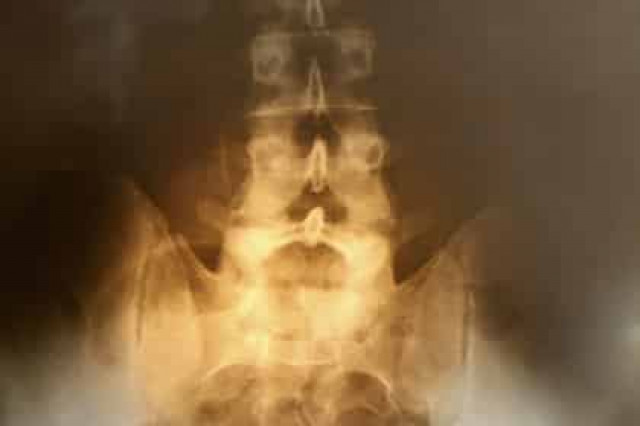

По словам исследователей, новая терапия имеет огромный потенциал для лечения спины и шеи, а также травм спинного диска, суставов и мышц.